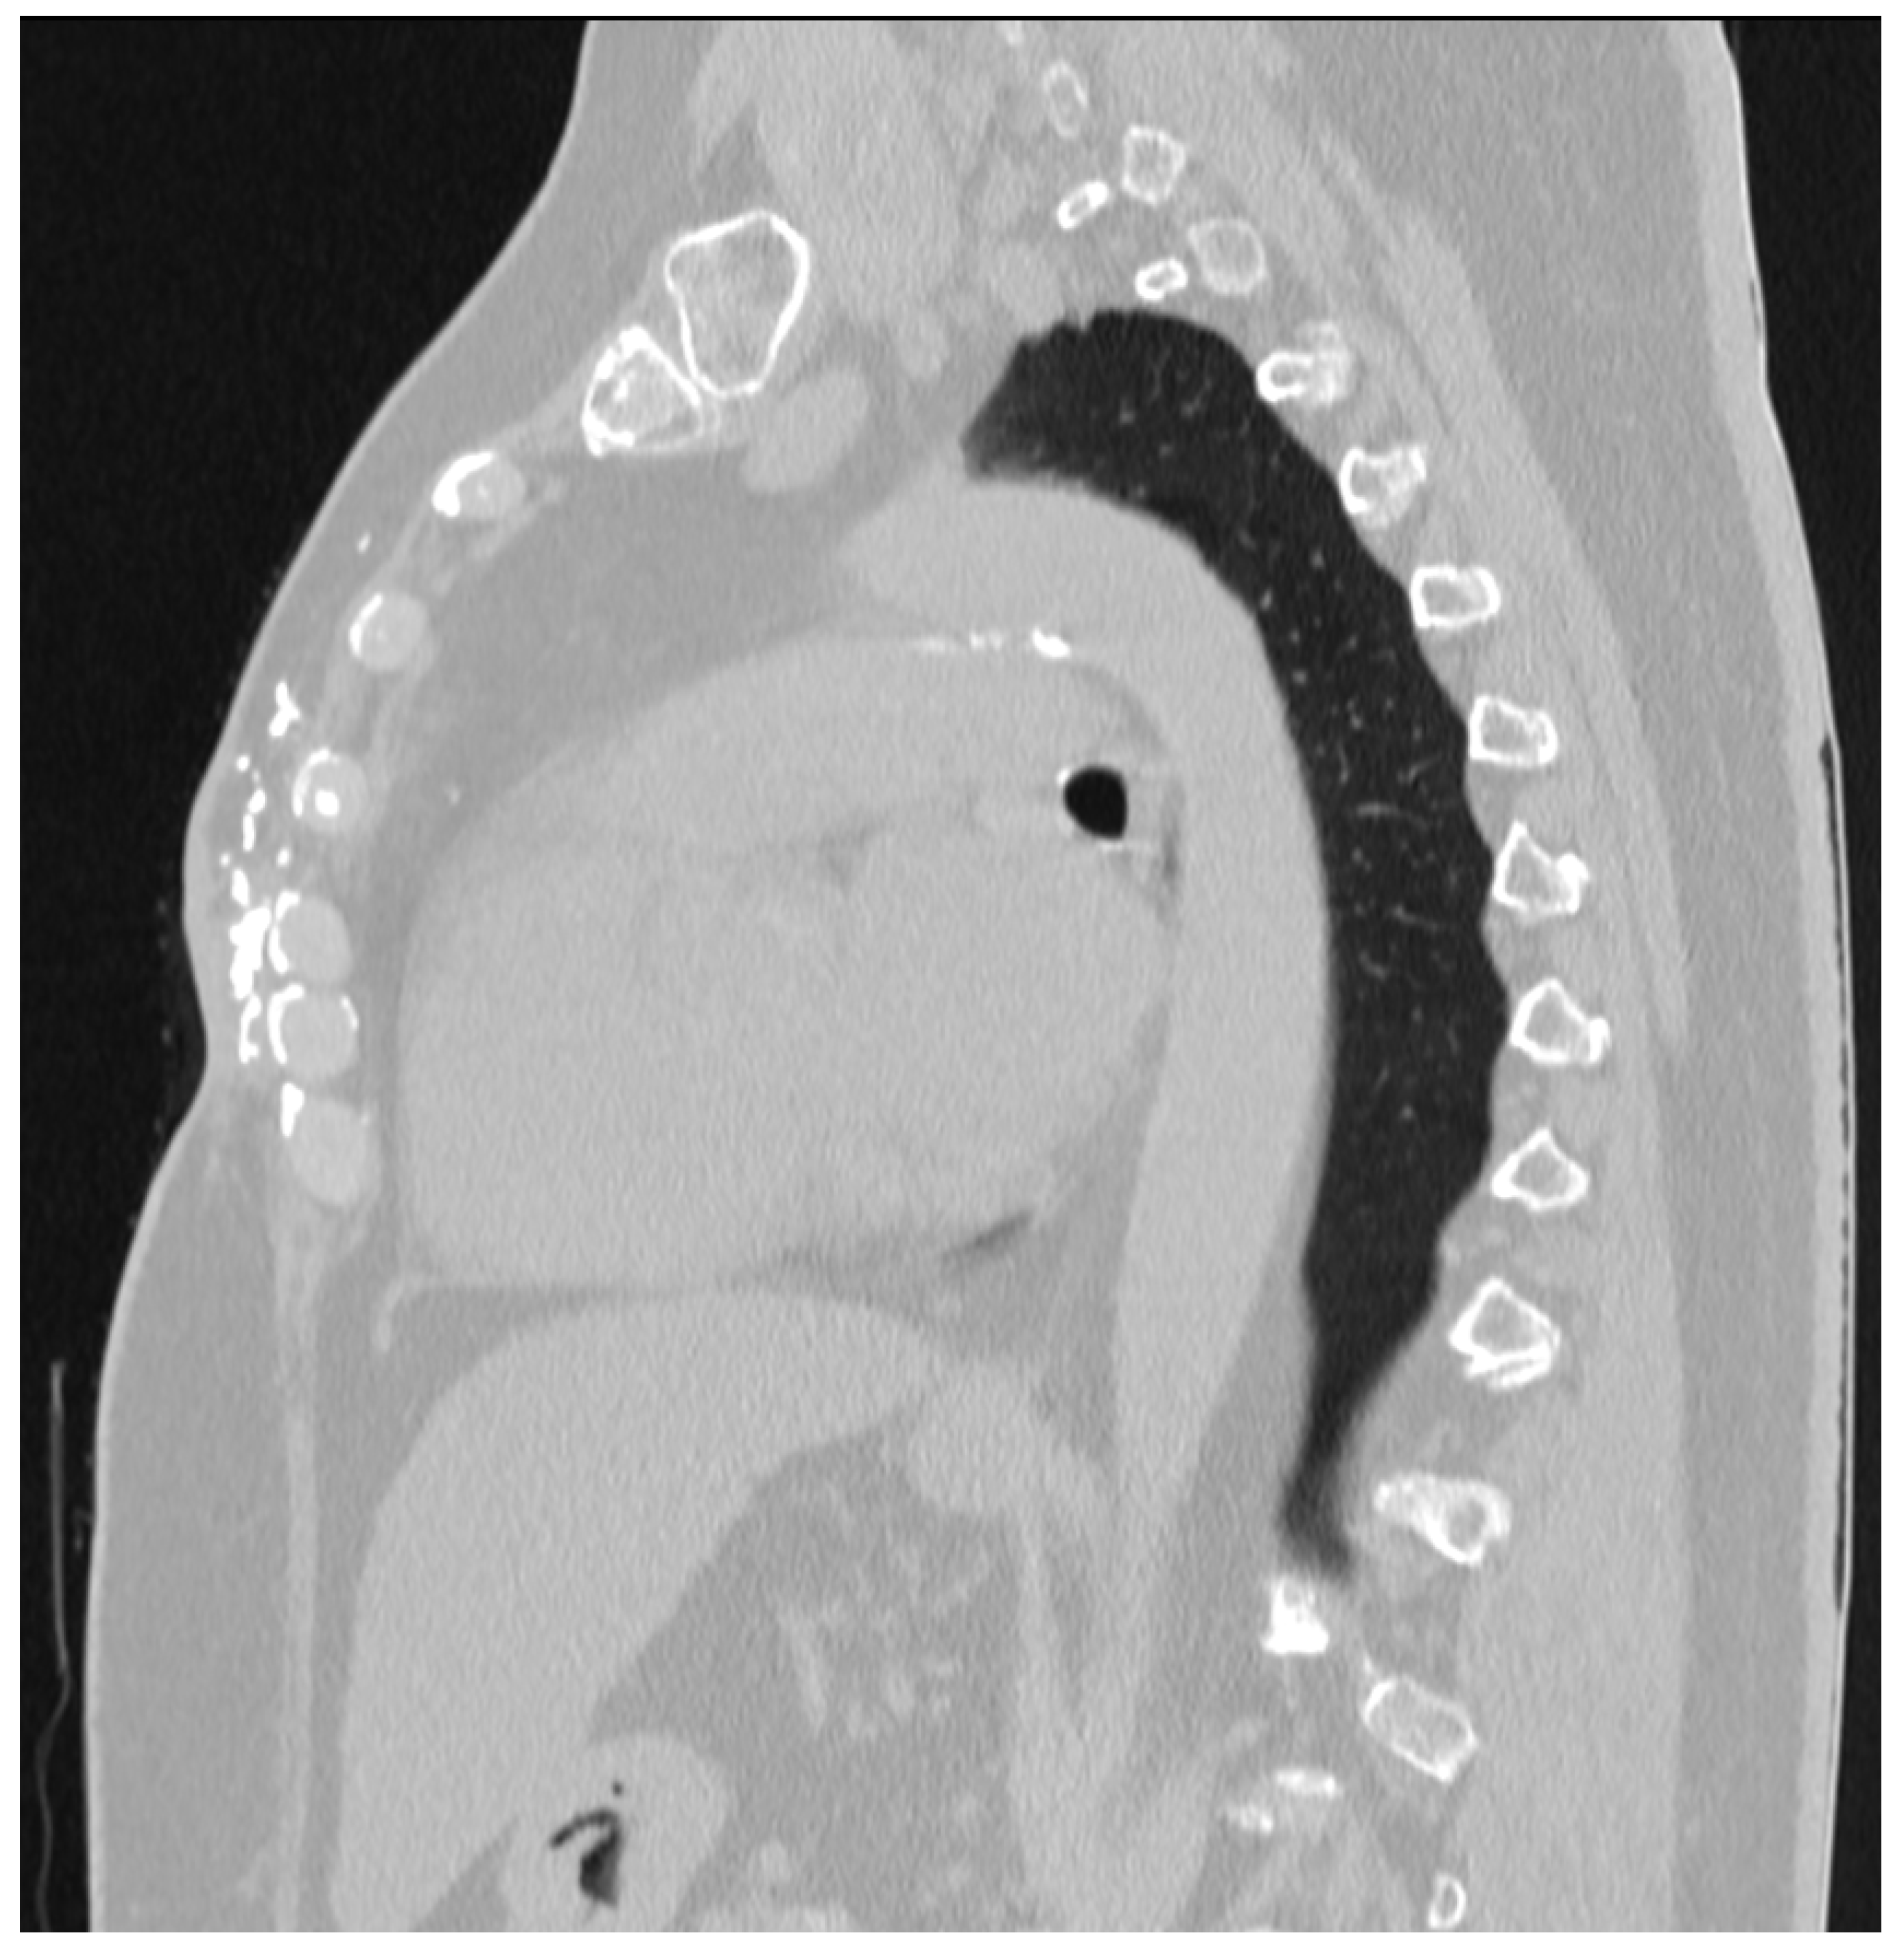

Symptomatic Calcifications after Mastectomy: A Rare Case Report with a Review of the Literature

2. Case Report